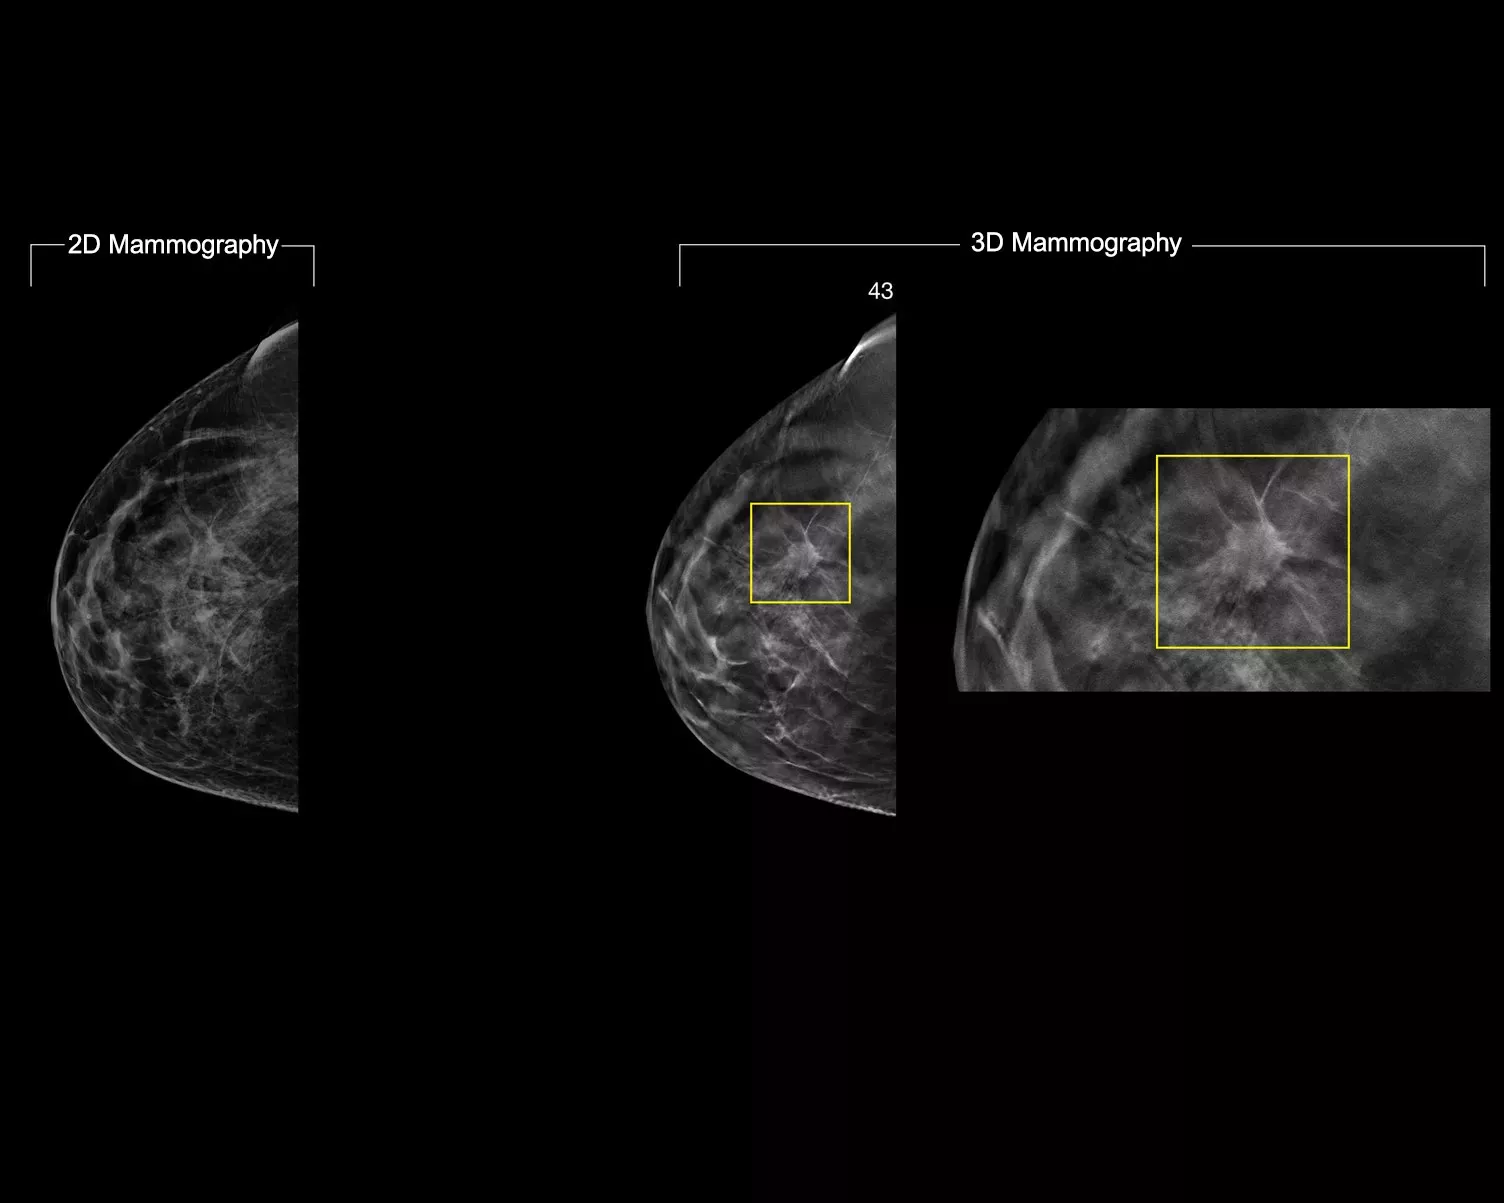

Die 3DQuorum™ Technologie verwendet Genius AI™ Algorithmen auf KI-Basis, um aus den hochauflösenden 3D-Mammografiedaten auf einzigartige Weise 6 mm Schichten, genannt SmartSlices, zu erzeugen. Diese verkürzen die Befundungszeit durch die Reduktion der zu befundenden Schnittbilder ohne Kompromisse bei Bildqualität, Sensitivität und Genauigkeit.2,3 Mit unserer bahnbrechenden Innovation ersparen Sie sich 1 Stunde Befundungszeit pro Tag.2,3*

Die Algorithmen von Genius AI erkennen ROI, Regionen von Interesse, und erhalten wichtige Merkmale während der Erstellung der SmartSlices.2 Die 3 mm Überlappung der SmartSlices bei 6 mm Stärke stellt sicher, dass keine Daten verloren gehen, und gewährleistet ein durchgehendes Scrollen.4-6

Durch die Auswertung von SmartSlices anstelle von 1-mm-Schichten reduziert sich die Anzahl der zu überprüfenden 3D™ Bilder um zwei Drittel.4-6 Dies bedeutet eine durchschnittliche Zeitersparnis von 1 Stunde pro Tag bei der Bildauswertung.3